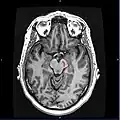

![]() Section through superior colliculus showing substantia nigra. | |

Horizontal MRI (T1 weighted) slice with highlighting indicating location of the substantia nigra.